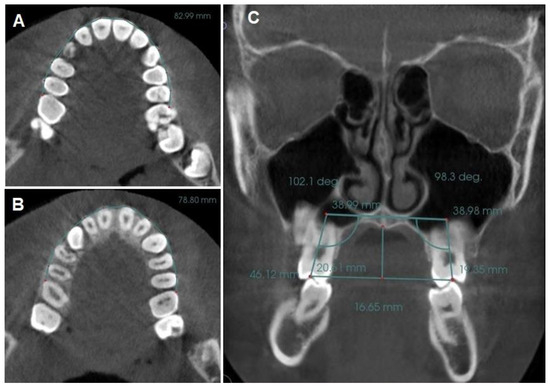

- Coronal perimeter (CP): the distance between the mesial of the right upper first molar and the mesial of the left upper first molar, passing through the vestibular side of all the teeth of the arch (Figure 2A).

- Angulation of the upper first molar (MA): the angle formed between a straight line drawn parallel to the hard palate plane (in sagittal view, utilizing the anterior nasal spine (ANS) and posterior nasal spine (PNS) as reference points) and a line passing through the center of the pulp chamber of both upper right and left first molars [12,55] (Figure 2C).

- Intermolar width (IMW): the distance between the central fossa of the upper right and left first molars was measured (Figure 2C).